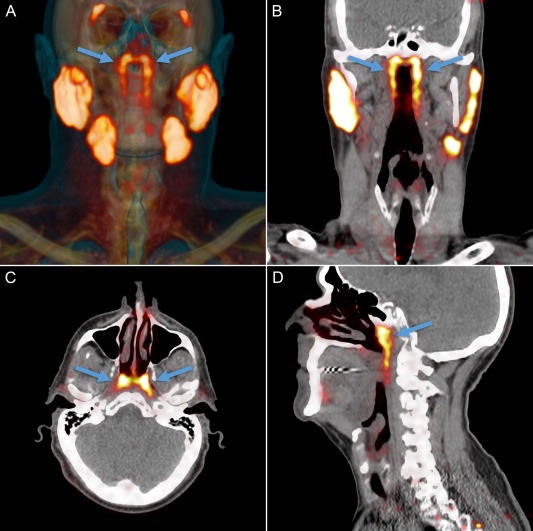

Четвертая пара слюнных желез расположена в геометрическом центре черепа, ближе к его основанию. Фото: thegreenjournal.com

Исследователи для обнаружения и визуализации опухоли в организме взяли меченую радиоактивными изотопами глюкозу. Специалисты обнаружили, что глюкозу поглощали не только опухоли, но и некие органы, которые и оказались четвертой парой слюнных желез.

Как выяснили медики, четвертая пара слюнных желез отвечает за смазку и защиту носоглотки и зева.